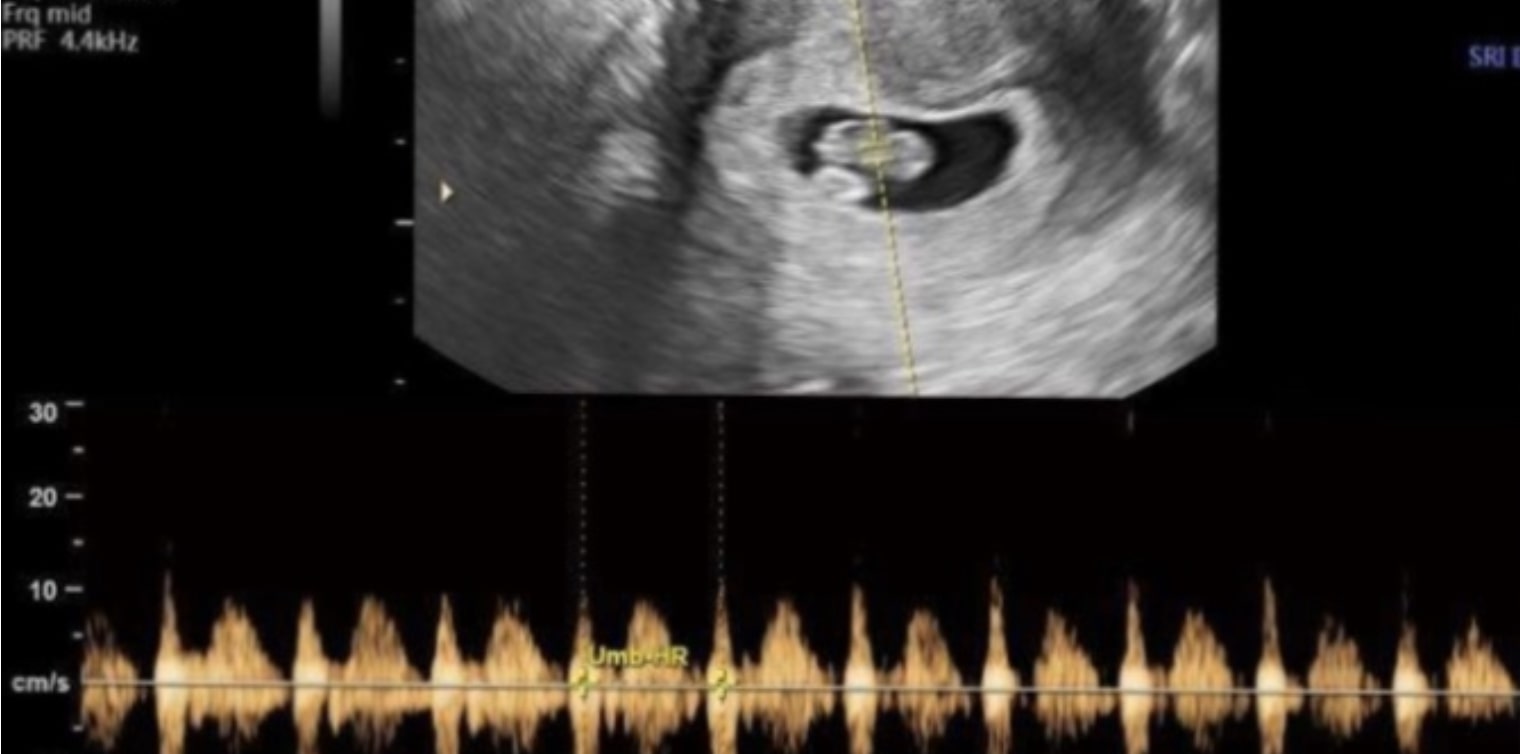

This is an important story for us because it highlights our focus and expertise. This patient started treatment with us over five years ago, and she was told by another IVF center that conception with her eggs was not possible, and her best option would be egg donation. Today she is about 12 weeks pregnant and her non-invasive chromosome testing came back negative/normal.

We used the patient’s egg, not a donor egg. Because of her extremely high FSH, the egg was stimulated using a “Suppression Stimulation,” which is a protocol involving only non-traditional oral medication such as birth control pills for “stimulation.” The egg was retrieved under local anesthesia, cultured, and frozen as a Day 3 embryo.

It is important to remember that we do have a long way to go until a healthy baby, but the heartbeat on the ultrasound showed that we are over 95 percent out of the woods.